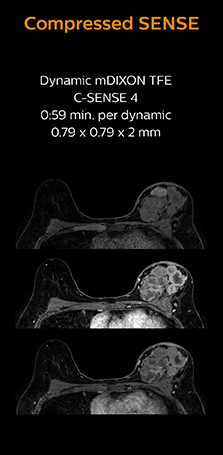

“In breast scanning, high resolution is important to help me identify very small mammary lesions, so, we need high spatial resolution in 2D T1- and T2-weighted images, as well as a short scan time. Compressed SENSE has allowed us to increase spatial resolution, which benefits our diagnostic confidence.”

Dr. Koyama says that he used to believe that high resolution MRI at 1.5T required long scan times, and SNR was low. “With Compressed SENSE, however, it is possible to acquire high quality images, even with higher Compressed SENSE factors, so in a quite short time.”

Dr. Koyama says that a C-SENSE factor of 4.0 was chosen to increase their spatial resolution in 3D dynamic breast scanning. “In addition to a high temporal resolution, we also require high spatial resolution, which helps us to see details of the internal structure of the lesion and to see lesions separately from normal anatomic structures. We can also see if a lesion extends into adjacent organs and anatomic structures.”

This patient underwent MRI on Ingenia 1.5T with Compressed SENSE. Compressed SENSE was used to reduce the scan time in order to decrease the time that the patient may experience discomfort and pain, both of which may lead to patient motion. The 3D BreastVIEW and 3D high resolution mDIXON images – both mDIXON contrasts are acquired in the same exam – show high quality images even with the shorter scan time. The spatial resolution of the dynamic scan with Compressed SENSE is higher than in the previous protocol (not shown) which allows for better visualization of the lesion with respect to the muscles of the thoracic wall and better delineation of small structures.

For breast imaging, a fast, high resolution scan can be important for a female patient having to lie in an uncomfortable, face-down position in the scanner. Compressed SENSE also helps us to obtain higher* quality images using 3D BreastVIEW and 3D high resolution mDIXON sequences in the same examination time as in our previous exam protocol.